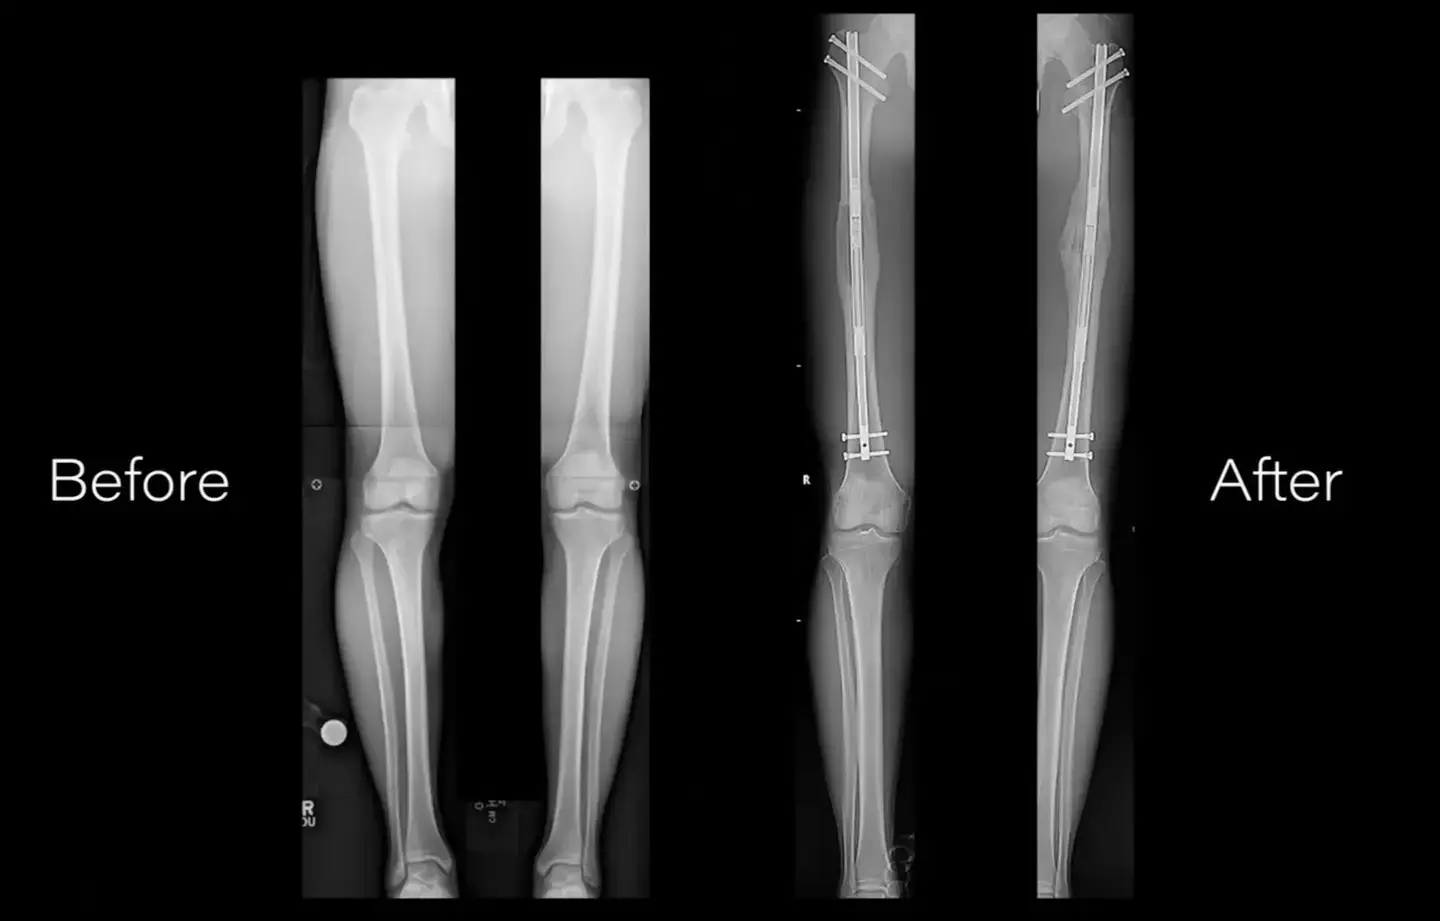

In a video uploaded to YouTube by NuVasiveInc, we quickly learn surgeons perform an osteotomy by cutting the affected bone into two segments.

A series of metal pins and braces are then implanted to the area around a break with a little screw sticking out.

The first involves an external fixator, which sees a metal frame usually sticking out several inches from the body.

Another option is to place an internal rod inside of the bone, and it's more aesthetically pleasing (I guess), as it's not seen outside of the body.

This gradually stretches out the leg as the bone is healing, until the point of desired length is reached for the patient.